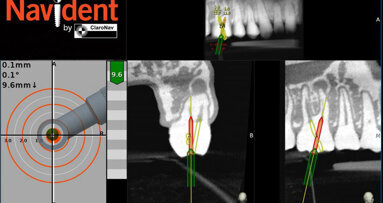

TORONTO, Ontario, CANADA: ClaroNav announced today (June 3, 2020) that it has obtained Health Canada and CE Mark approvals to expand the indications for use...

TORONTO, Ontario, CANADA: Azento single tooth replacement solution is transforming the digital implant workflow by streamlining implant planning, purchasing...